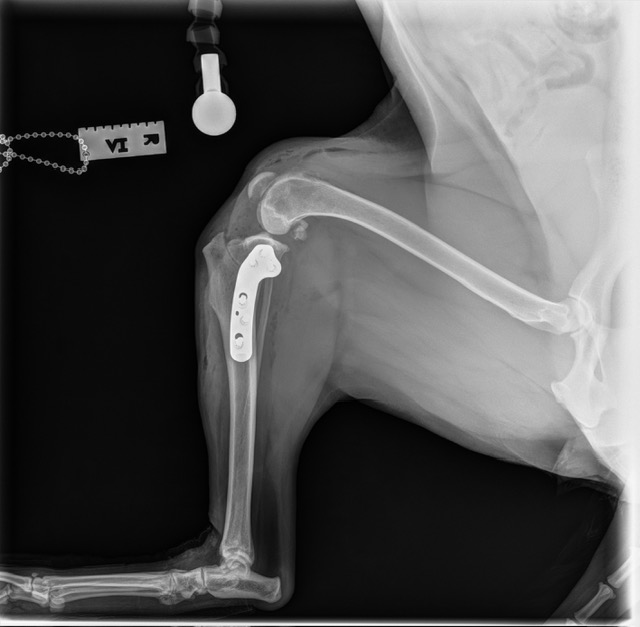

Tibial Plateau Leveling Osteotomy (TPLO)

TPLO is a surgical technique that stabilizes the knee by altering the biomechanics of the joint. By changing the angle of the tibial plateau, the procedure eliminates the need for the cranial cruciate ligament during weight bearing, helping to improve comfort and function during movement.

Tibial Plateau Leveling Osteotomy (TPLO) #1

Tibial Plateau Leveling Osteotomy (TPLO) #2

Tibial Plateau Leveling Osteotomy (TPLO) #3